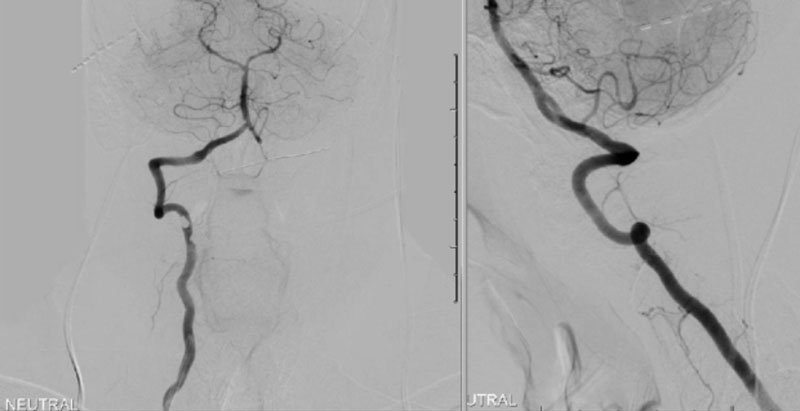

We performed conventional catheter angiography with provocative testing to reproduce his symptoms. The right Vertebral Artery is the codominant primary supply to the basilar circulation with reflux into the distal left Vertebral Artery that is occluded (Figure 3).

During neutral positioning, the vertebrobasilar circulation fills briskly from the Right Vertebral Artery. (Figure 4)